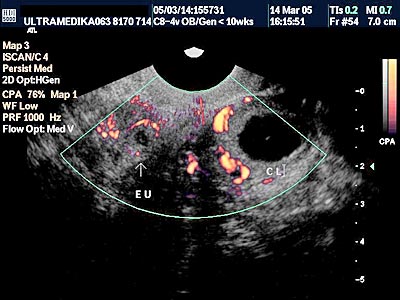

D) Četvrti UZ marker koji mora biti proveren je procena PI (pulzativnog indeksa) tj. procena otpora proticanju krvi kroz venski sud koji dovodi krv u srce ploda i naziva se Duktus venozus! Ova struktura je veličine nekoliko milimetara i pouzdano se može kodirati Braund Band CD i kolor Power Dopplerom. Praktično samo aparati velikih mogućnosti koji koriste ovu tehniku mogu u velikom procentu tj kod većine trudnoća u ovoj gestacionoj starosti registrovati patološki protok u Duktusu venozusu!

Inače patološki protok u ovom malom krvnom sudu je od velikog značaja jer može ukazivati da plod ima hromozomsku anomaliju ili urođenu srčanu manu!